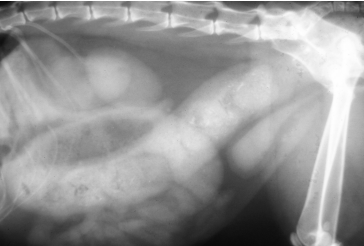

Dt: R-Lateral abdominal rads, double bubble, ↑ PCV, metabolic acidosis, coagulation defects

Dt: r/o GDV →R-Lateral abdominal rads w/ uniform food-filled stomach

No volvulus present, rule out GDV

Dt: PE, Palpation, survey Rads #1 ± contrast, US(more sensitive)

dilated loops, stacking, gas pattern

Comma-shaped gas bubbles